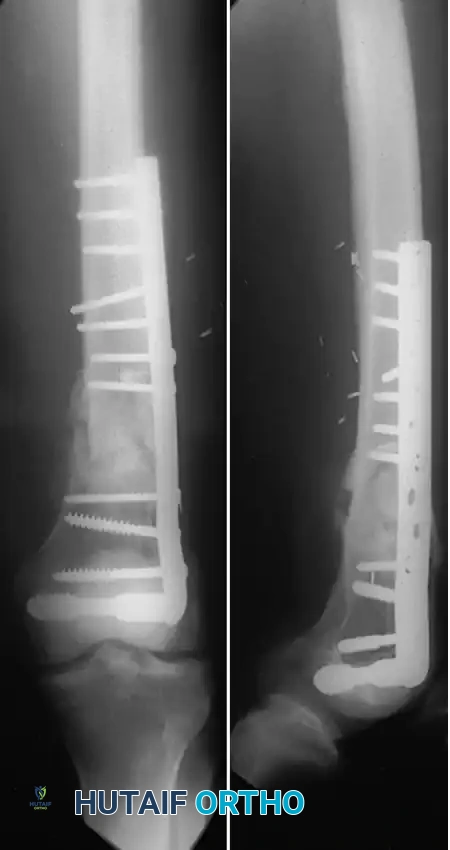

Condylar Buttress Plates and Dual Plating

For fractures with less than 3 to 4 cm of intact condylar bone, or those with massive articular comminution, blade plates and DCS constructs are unsuitable. In these scenarios, the condylar buttress plate is utilized. Its multiple distal holes allow for targeted screw placement into small, comminuted articular fragments.

Image

Condylar buttress plate applied to a highly comminuted distal femur fracture.

Multiple distal screws capturing independent articular fragments.

However, a lateral buttress plate alone may fail in varus collapse if there is severe medial comminution or segmental bone loss. To counteract this, dual plating is often required. Chapman and Henley advocated the addition of a medial plate (often an inverted large fragment T-plate) inserted through a separate medial subvastus incision.

Dual plating technique utilizing a lateral buttress plate and a medial stabilization plate.

Radiographic appearance of a dual-plated distal femur, providing rigid bicolumnar support.

Jazrawi et al. further advanced this concept by describing a locked dual plating technique, which provides superior biomechanical stability in osteopenic bone. Because extensive dual approaches can lead to wound healing complications, percutaneous locked plating techniques have become the gold standard for bridging highly comminuted metaphyseal segments while preserving the vascular supply.